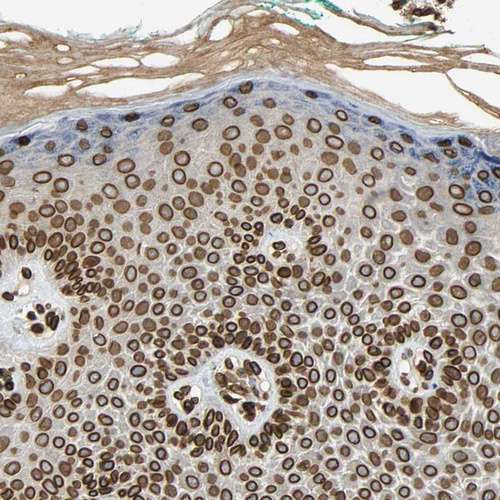

Immunohistochemistry analysis in human skin and bone marrow tissues using HPA008461 antibody. Corresponding SUN1 RNA-seq data are presented for the same tissues.